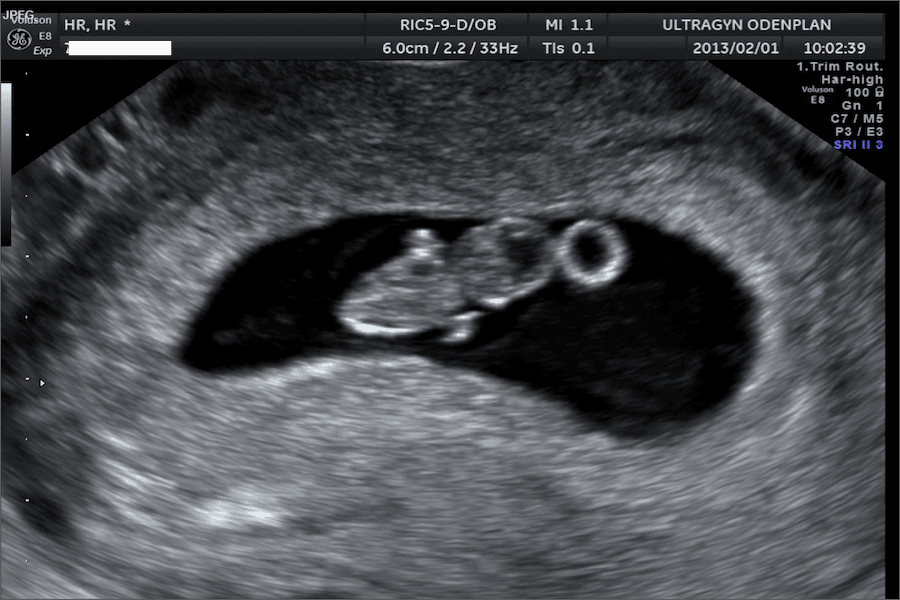

Ett tidigt ultraljud är ett ultraljud som görs någon gång mellan vecka 6 och 12. Den här typen av ultraljud görs för att bekräfta att graviditeten är viabel (det vill säga att det finns hjärtaktivitet), att själva graviditeten sitter där den ska i livmodern, hur många barn som finns där inne samt för att försöka bestämma graviditetslängd. Ibland är det för tidigt att beräkna graviditetslängd och då kommer du rekommenderas ett nytt ultraljud ett par veckor senare.

Innan vecka 10 kan det vara svårt att se graviditeten med en dosa som läggs utanpå magen, därför behöver man ibland göra ett vaginalt ultraljud. Då använder sig läkaren eller barnmorskan av en ultraljudsstav som förs upp i slidan med hjälp av glidmedel. Det kan kännas obehagligt och vissa kvinnor kan uppleva lätt smärta, men det är inget som är farligt, utan går att jämföra med en gynekologisk undersökning.